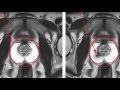

Рак шейки матки: причины развития и симптомы

Рак шейки матки: современные методы лечения